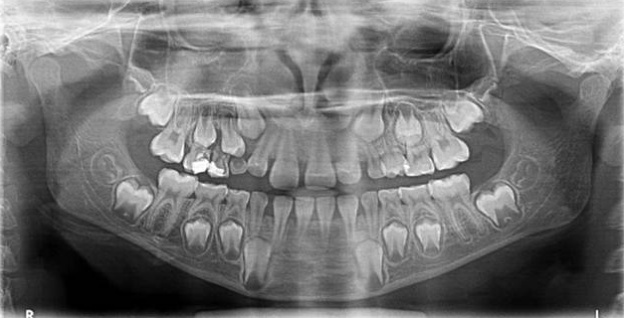

Radiologie

Le cabinet est équipé d’un appareil radiologique KODAK 8000 ceph permettant la réalisation de panoramique et de téléradiographie nécessaires à la réalisation des bilans orthodontiques et au suivi thérapeutique. Ces radiographies numérisées sont de qualité optimale avec des doses minimales d'irradiation.